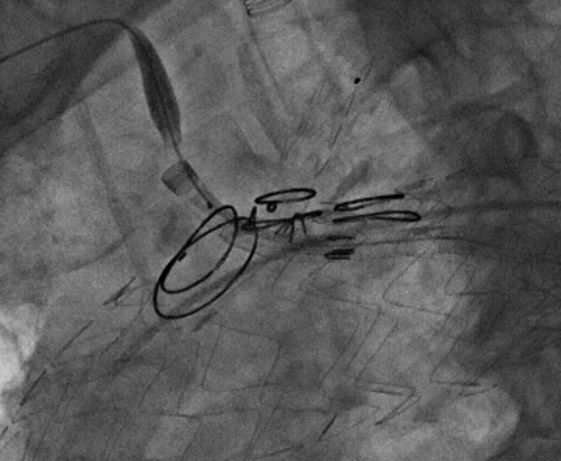

术前造影

导入弓部

主体支架

释放弓部

超选左颈总动脉

超选无名动脉

并预置导丝

导入左颈总

支架并释放

导入无名动脉

超选左锁骨下

动脉

导入左锁骨下动脉

导入并释放远端支架

术前

术后

手术用时115分钟